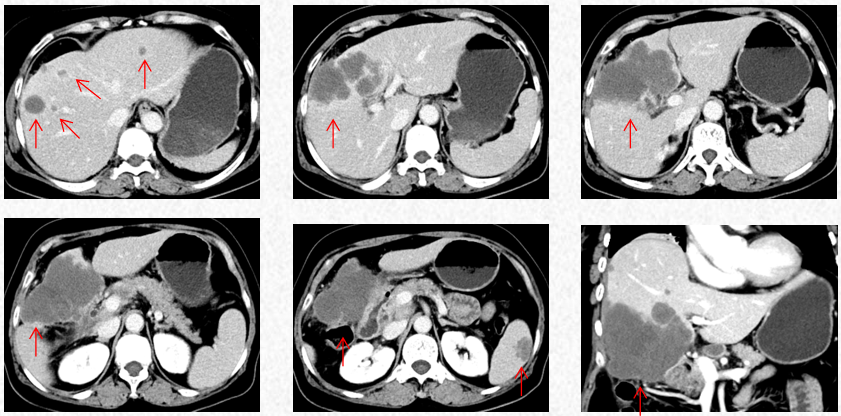

2023-3-19复查胸腹CT图片,最佳疗效评估为PR。

2023-5-22复查胸腹CT图片,疗效评估为SD,出现轻度双上肢麻木,可耐受。

2023-7-15复查胸腹CT图片,疗效评估为SD,轻度双上肢麻木,生活不受影响。

2023-3-19胸腹CT:肝肿物最大横截面积91*60mm,脾脏转移瘤(19*12mm)

2023-5-22胸腹CT:肝肿物最大横截面积86*58mm,脾脏转移瘤(19*12mm)

2023-7-15胸腹CT:肝肿物最大横截面积86*58mm,脾脏转移瘤(19*12mm)